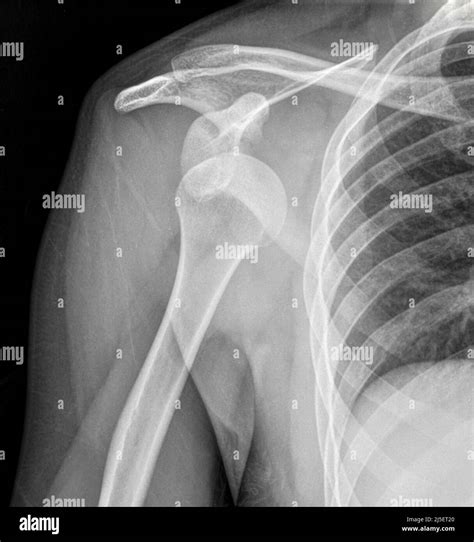

Typically, the technician will request at least two or three different views of the shoulder to ensure a comprehensive diagnosis:

• Anteroposterior (AP) View: Taken from the front, this view helps doctors see the general relationship between the humerus and the socket.

• Axillary View: This view captures the shoulder from underneath, which is crucial for identifying if the bone has moved forward or backward.

• Scapular Y View: This provides a lateral perspective, allowing the radiologist to see if the humeral head is centered in the socket of the scapula.

Following the confirmation provided by the Dislocated Shoulder X Ray, the medical team will proceed with reduction. Once the shoulder is back in its proper position, the doctor will often order a post-reduction X-ray. This second round of imaging is vital to confirm that the bone is correctly seated and that no new fractures were created during the reduction procedure.